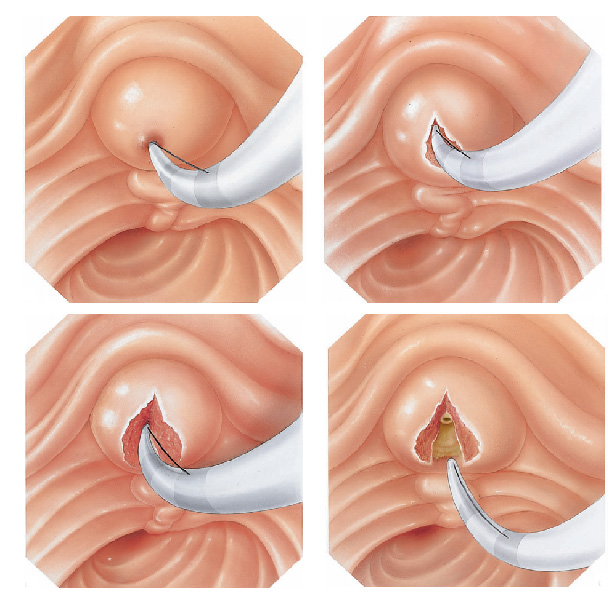

Realizada em quase todos os exames de colangiopancreatogragia retrógrada endoscópica (CPRE), a papilotomia endoscópica é o procedimento de abertura do ducto biliar comum. Tem o objetivo de alargar a abertura da papila duodenal para a drenagem da bile com maior facilidade e para retirada de cálculos que podem estar obstruindo a saída da bile. Também é utilizada em cados de estreitamentos da via biliar, para que se possa utilizar os instrumento de dilatação como as próteses plásticas ou autoexpansíveis.

Apesar da palilotomia por endoscopia ser menos agressiva que a realizada por cirurgia, ela também possui riscos, como sangramento e perfuração do intestino delgado. Estas quando ocorrem, geralmente são tratadas no mesmo momento por endoscopia, mas eventualmente pode haver necessidade de realização de cirurgia para a correção do problema.

Durante a CPRE, após a cateterização da via biliar e infusão de contraste, realiza-se o RX, que pode mostar cálculos (pedras) que podem estar obstruindo a saída da bile e causando os sintomas no paciente.

Após este diagnóstico realiza-se o procedimento de papilotomia endoscópica, para poder alargar a saída do canal da bile. Com isto pode-se retirar as pedras da via biliar e permitir o retorno normal da drenagem da bile do fígado para o duodeno.

Geralmente a simples abertura da saída do canal da bile não é suficiente para que o cálculo saia. Nestes casos precisamos inserir instrumentos através do duodenoscópico como cestas ou balões para varrer de cima para baixo o canal da via biliar e assim conseguir extrair os cálculos.

Quando o calculo é muito grande, precisamos quebrá-lo para poder retirá-lo, este procedimento é chamado de litotripsia mecânica. Este é realizado através da captura do cálculo com uma cesta, sendo esta fechada até que o cálculo quebre.

Eventualmente se o cálculo não quebrar ou se for de tamanho muito grande, pode-se realizar a passem de prótese através da abertura, para drenar a via biliar e desobstruir a região.

Geralmente após realiza-se o exame novamente alguns dias depois para uma nova tentativa de retirada do cálculo por endoscopia. Se as tentativas por endoscopias falharem o paciente é submetido a cirurgia para a resolver definitivamente o problema.

A CPRE pode ser utilizada para o tratamento de pedras ou bloqueios nos canais biliares. Seu médico pode usar alguns acessórios para fazer um pequeno corte na parede do intestino, na abertura do duto biliar comum para alargar a abertura da papila duodenal. Este procedimento chama-se papilotomia endoscópica.

Após este procedimento, pode ser possível a retirada de cálculos da via biliar, permitindo assim o retorno normal da drenagem da bile do fígado para o duodeno.